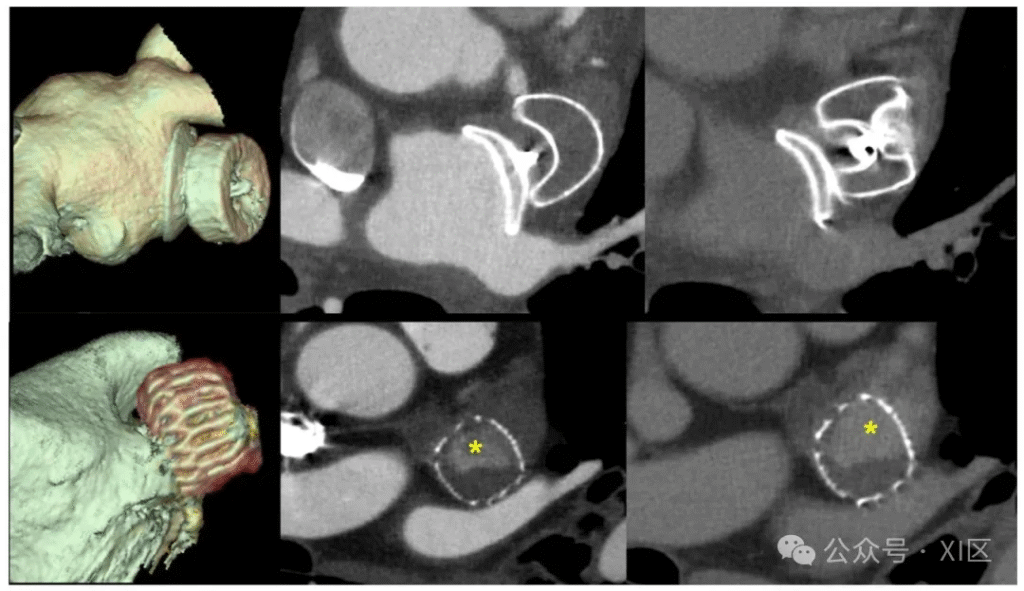

采用心脏计算机断层扫描(CCT)对拟行肺静脉隔离术的房颤患者进行左心耳(LAA)评估,分别展示动脉期(左图)与延迟期(右图)成像结果。左上图为左心耳无血栓的典型案例,两期成像均显示正常造影剂强化;右上图为左心房严重扩大患者的慢血流现象案例,动脉期左心耳远端部分造影剂分布不均且强化缺失,而延迟期左心耳则呈均匀造影剂充盈。下图为左心耳迁移性血栓案例,动脉期左心耳近端出现充盈缺损,且该缺损在延迟期成像中持续存在 。